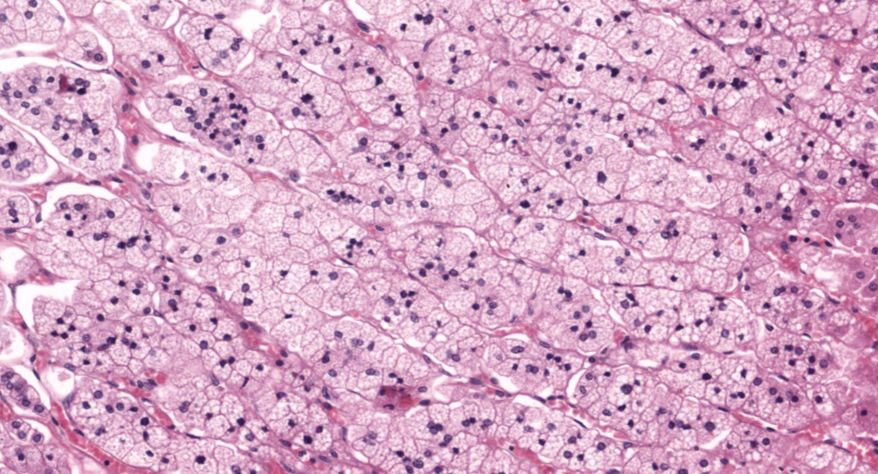

低倍镜观察:1. 被膜:由薄层结缔组织组成。2. 实质:由许多大小不等的滤泡构成。滤泡壁是单层立方上皮细胞,滤泡腔内充满粉红色匀质胶状物,滤泡之间的结缔组织内有丰富的血管。高倍镜观察:1. 滤泡:滤泡壁的单层滤泡上皮细胞一般呈低柱状或立方状,胞质着浅色,细胞核呈圆形。滤泡腔内充满了粉红色匀质胶质。2. 滤泡旁细胞:体积较大,呈圆形或椭圆形;细胞核较大,呈圆形,着色较浅,细胞质染色也较浅。细胞或嵌在滤泡壁上或成团分布于滤泡之间。3. 间质:由结缔组织组成。位于滤泡之间。其中含有丰富的毛细血管及三五成群的滤泡旁细胞。

1.全景图

2.滤泡

3.滤泡上皮细胞

4.胶质

5.滤泡旁细胞1

7.滤泡旁细胞2